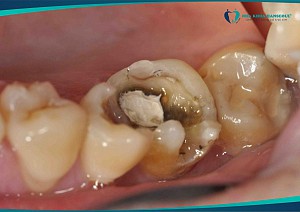

- Răng mọc thẳng nhưng sâu vỡ lớn dẫn đến viêm tủy khó điều trị do nằm trong cùng nên hạn chế khả năng quan sát của bác sĩ.